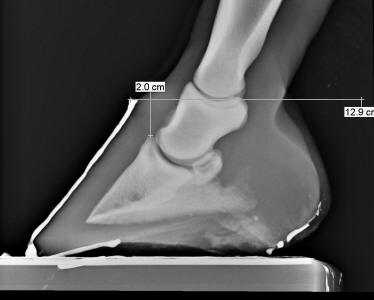

As detailed last month, your farrier (or you) may realize

your horse has a coffin bone position that is too deep in the hoof capsule

because the heels and/or toes are longer-than-normal, in spite the fact that the

sole is NOT excessively thick—these feet cannot simply be shortened to an

optimal length without excessively thinning the sole. Your veterinarian may also

diagnose this condition by using a lateral radiograph to compare the “height of”

the top of the coffin bone to the “height of” the top of the hoof capsule

(coronet-to-extensor process or CE

measurement, see Figure 1).

At

first glance, this hoof may appear healthy—no rotation or flaring, and an

adequately thick sole. But a timely visit from the veterinarian revealed a good

reason for low performance and general unsoundness. The CE measurement is 2

centimeters (about 7/8th inch)—a quite severe case. This problem is

often overlooked until it is too late. Photo reprinted from the book Care and

Rehabilitation of the Equine Foot.